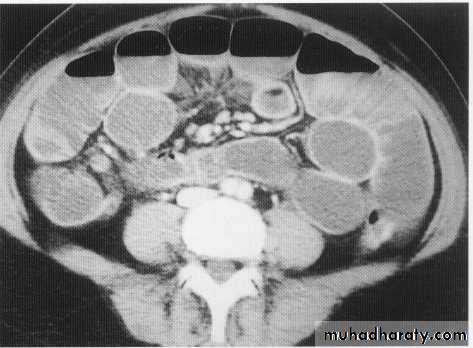

Barium follow throw x- rayCt scan with oral contrast

Ct scan with i.v contrast

Stricture + pericolic abscess